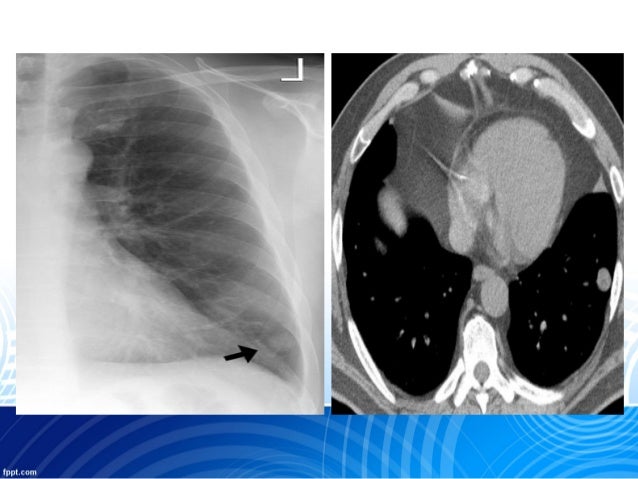

What is a lung nodule?

Depending on their attenuation in CT imaging, lung nodules are categorized in three different types: (i) solid nodules, the most common type, characterized by homogeneous soft-tissue attenuation, (ii) ground-glass nodules, nonuniform in appearance with a hazy increase in local attenuation of lung parenchyma not obscuring the underlying bronchial and vascular structures, and (iii) part-solid no dules, comprising both solid and ground-glass attenuation components.

Generally, a pulmonary nodule must grow to at least 1 cm in diameter before it can be seen on a chest X-ray. An SPN is surrounded by normal lung tissue and is not associated with any other abnormality in the lung or nearby lymph nodes (small, bean-shaped structures found throughout the body).